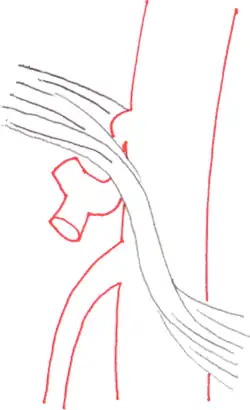

The median arcuate ligament is a ligament formed at the base of the diaphragm where the left and right diaphragmatic crura join near the 12th thoracic vertebra. This fibrous arch forms the anterior aspect of the aortic hiatus, through which the aorta, thoracic duct, and azygos vein pass. The median arcuate ligament usually comes into contact with the aorta above the branch point of the celiac artery. However, in up to one quarter of normal individuals, the median arcuate ligament passes in front of the celiac artery, compressing the celiac artery and nearby structures such as the celiac ganglia.[2] In some of these individuals, this compression is pathologic. It leads to the median arcuate ligament syndrome.[2]

Further evaluation and confirmation can be obtained via angiography to investigate the anatomy of the celiac artery.[5] Historically, conventional angiography was used, although this has been largely replaced by less invasive techniques such as computed tomography (CT) and magnetic resonance (MR) angiography.[2][5] Because it provides better visualization of intra-abdominal structures, CT angiography is preferred to MR angiography in this setting.[5] The findings of focal narrowing of the proximal celiac artery with poststenotic dilatation, indentation on the superior aspect of the celiac artery, and a hook-shaped contour of the celiac artery support a diagnosis of MALS.[2] These imaging features are exaggerated on expiration, even in normal asymptomatic individuals without the syndrome.[2]

Proximal celiac artery stenosis with poststenotic dilatation can be seen in other conditions affecting the celiac artery.[2] The hook-shaped contour of the celiac artery is characteristic of the anatomy in MALS and helps distinguish it from other causes of celiac artery stenosis such as atherosclerosis.[2] This hooked contour is not entirely specific for MALS however, given that 10–24% of normal asymptomatic individuals have this anatomy.[2]